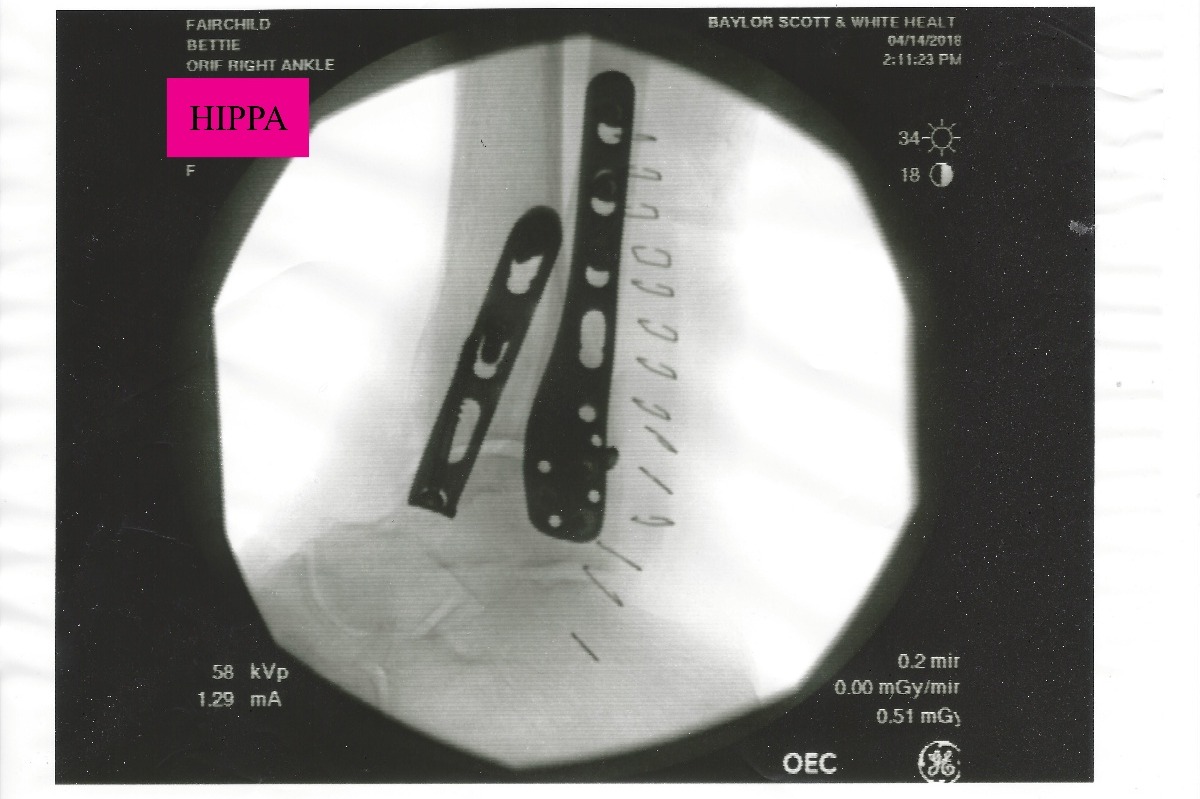

However, the move has not been as smooth as they would have liked. In February, Bettie was hospitalized for an infection and had to go to rehab to regain her strength. On April 12th, Bettie fell in her bathroom and broke her right ankle in 4 places as well as dislocating it. The break was a compound fracture and she needed emergency surgery (Photos Below).